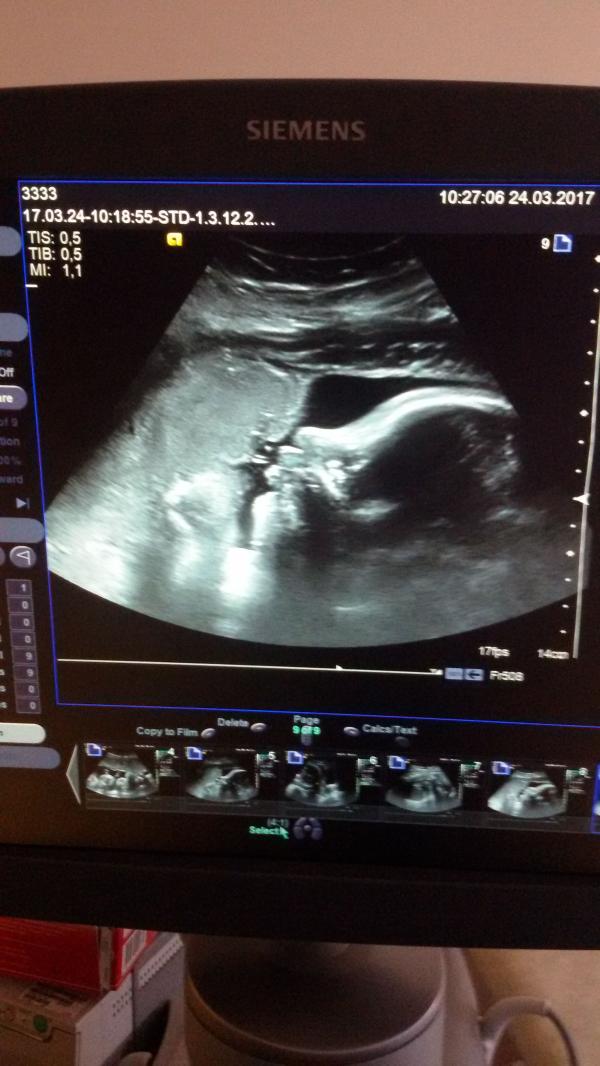

Вчера был третий скрининг^.^ Мы так и остались девчонками, весим 2130 гр.😍😍😍😍 Шейка удлиннилась с 34 мм до 40 мм. Хочу уже увидеть свою кроху😤 я наверное, одна такая не нормальная, которая бы уже хоть сейчас побежала рожать 😐